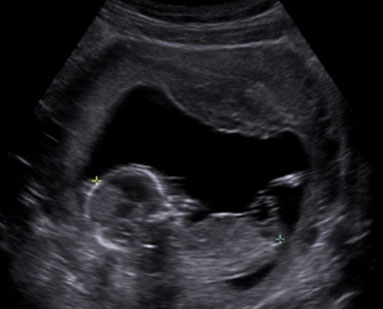

This was the first pregnancy of a 26-year old woman expecting monochorionic twins. She was first seen at 12 weeks and was followed up closely by a fetal medicine specialist with experience in the care of monochorionic twins at least fortnightly. It was obvious that Twin B’s estimated fetal weight was significantly larger than that of Twin A from 15 weeks, and this difference continued to increase as the pregnancy progressed (Figure 1). Discordances were seen in the abdominal circumferences and femur lengths. At 15 weeks gestation, the umbilical artery showed persistently positive end-diastolic flow in Twin A. This suggested that it was type I sIUGR. At 17 weeks, the Doppler studies showed persistently absent end-diastolic flow in the umbilical artery which corresponded to type II sIUGR (Figure 2). This raised concerns regarding the survival of Twin A as there was a 90% chance of deterioration of this fetus. Thus, we considered the following options for the twins: (1) expectant management with close monitoring of their arterial and venous Dopplers, (2) selective laser photocoagulation of the placental vascular, (3) cord occlusion of twin A, and (4) abortion of the whole pregnancy. With type II sIUGR diagnosis, cord occlusion of the umbilical cord of Twin A was considered to eliminate the risk of acute twin-to-twin transfusion from the bigger to the smaller twin if the smaller twin was to die in-utero. Three days later, a repeat scan, however, showed, intermittently absent and reverse end-diastolic flow of the umbilical artery (Figure 3). This changed the diagnosis to type III sIUGR. This case, thus, showed unique Doppler changes from a classification of type I to II to III sIUGR. The intermittent nature of the Doppler studies of the umbilical arteries could explain why it was first thought to be type I, then type II, and finally, type III sIUGR (Figure 4). At 32 weeks, head circumference for both Twins A and B were similar, whereas the abdominal circumferences and femur lengths for Twin A were significantly lower. The timing of the delivery was discussed with the couple and the neonatologist. As the estimated weight discordance was large at about 50% (2 and 1 kg for the Twins B and A, respectively), and the possibility of an unexpected death of the smaller twin with risk of death and morbidity to the other twin was significant, a joint decision was made to deliver the babies at 32 weeks. Corticosteroids were administered and caesarean section was performed. At delivery, the weights of Twins A and B were 1.8 and 1.2 kg, respectively, with birth weight discordance of 30%. The placenta was examined. The veins were injected with white dye and arteries injected with blue dye. Twin B’s bigger umbilical cord was centrally inserted, while that of Twin A was marginally inserted (Figure 5). The vascular equator is along the dotted line, where it shows that about 75% of the placenta belong to Twin B, while the other 25% belong to Twin A. The unequal placental sharing and the presence of an AAA (circled) validated the sIUGR type III diagnosis as these are known characteristics of this diagnosis (Figure 5). Both babies are developing well although there was mild respiratory distress syndrome (RDS) in the first few days that subsequently resolved.

Figure 2: Doppler ultrasound of Twin A’s umbilical arteries, showing absent end-diastolic flow (type II) at 17 weeks.